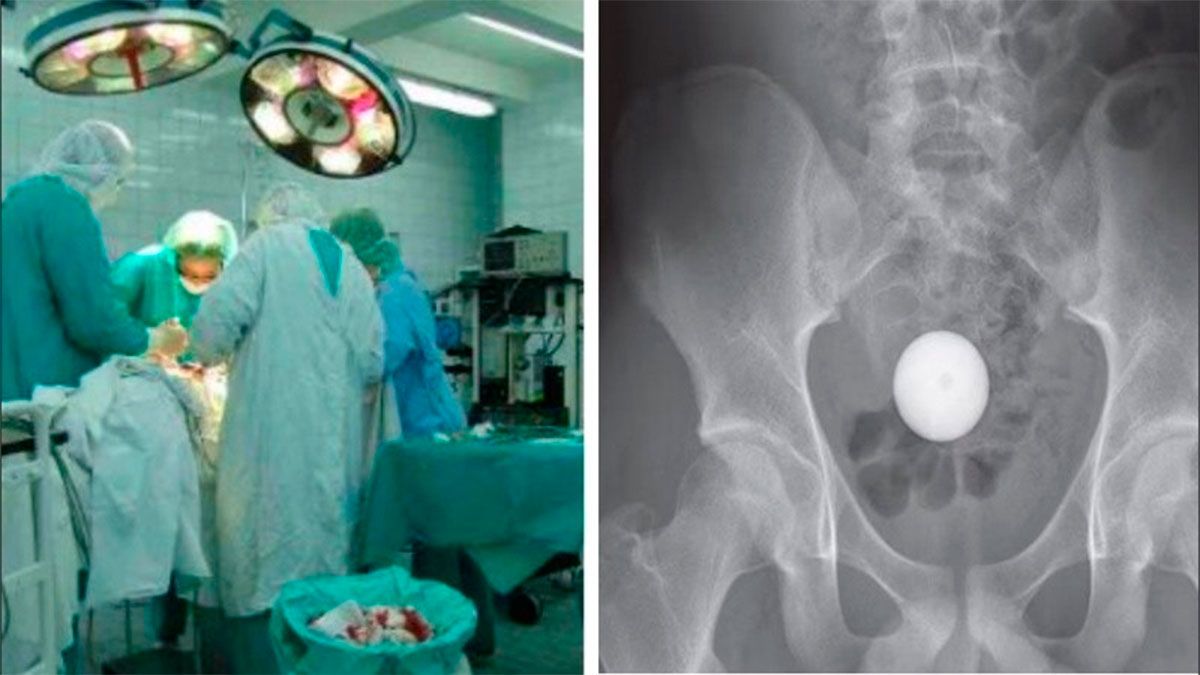

Una pelota de golf quedó atrapada en el intestino de un adolescente después de que se lo metiera en el ano. El joven de 14 años, de Australia, entró en pánico cuando se dio cuenta de que no podía sacar la pelota.

El adolescente, que no fue identificado, también confesó que había intentado sin éxito expulsar la pelota al defecar. Los escaneos de rayos X mostraron que había llegado a su colon sigmoide, la última parte del intestino grueso, que se conecta con el recto.

Los médicos trataron de extraer la pelota de golf utilizando seis dispositivos de recuperación diferentes, incluida una ventosa, una red médica, una pinza de cuatro puntas y un catéter con balón.

Después de dos horas, los médicos se dieron por vencidos con la esperanza de que la pelota de golf saliera sola. Sin embargo, una radiografía realizada 24 horas después mostró que todavía estaba allí.

Al niño se le dio un litro de laxantes, lo que resultó en la "evacuación exitosa" de la pelota de golf tres horas después.

"Después del paso de la pelota de golf, el paciente permaneció clínicamente bien y fue dado de alta el mismo día", dijeron los investigadores. Agregaron que al joven "se le aconsejó que no insertara más objetos en su recto en el futuro".

Los médicos concluyeron: "Una pelota de golf presenta desafíos técnicos únicos cuando se intenta extraer del colon debido a sus propiedades mecánicas. Estos incluyen su gran tamaño, forma esférica, incompresibilidad y la presencia de hoyuelos, lo que impide un sello de succión".